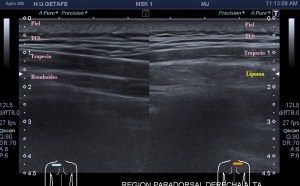

Los vientres anteriores de los músculos Digástricos, que son el objeto del desarrollo de este Post, son dos estructuras musculares redondeadas en el corte transversal, imagen 1, y alargados si los estudiamos en el eje largo, imagen 3, mira:

Ecográficamente los músculos digástricos en eje corto tienen semiología hipoecogénica, en aspecto de noche estrellada, como la de hoy, y en el eje largo en forma de penacho o en forma de plumas con las fibras alargadas y paralelas a la superficie.